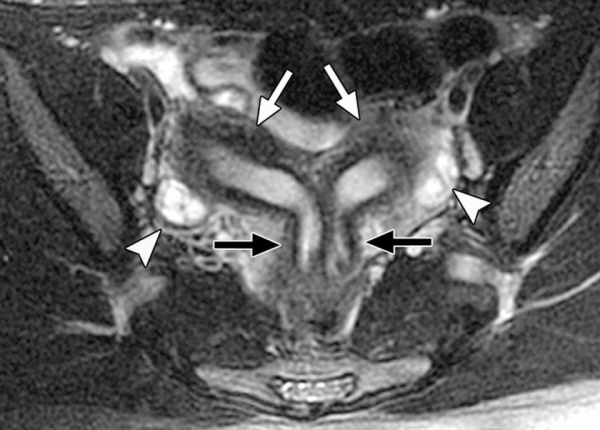

- МРТ малого таза. Назначают при подозрении на аномалии развития внутренних половых органов. С помощью томографии можно определить строение и положение матки, яичников.

Вид аномалии устанавливается на основании гинекологического осмотра и данных дополнительных исследований. Для уточнения особенностей аномалии развития матки используют инвазивные исследования – гистероскопию и лапароскопию, которые позволяют оценивать форму, объем и состояние внутренней полости матки, определять структуру, выявлять сопутствующую патологию фаллопиевых труб и другие нарушения. Современной альтернативой инвазивному исследованию становятся нетравматичные МРТ и УЗИ с высоким разрешением.

Пороки развития матки выявляется, как правило, случайно. О наличии врожденной патологии женщина может не догадываться. При выраженной деформации дна матки нередко наблюдается первичное бесплодие, которое и заставляет пациентку обратиться к врачу. Стандартное гинекологическое исследование при седловидной и двурогой матке малоинформативно. В диагностике врожденных аномалий матки решающая роль отводится инструментальным исследованиям – УЗИ органов малого таза, гистероскопии, гистеросальпингографии, магнитно-резонансной томографии (МРТ). При обнаружении порока для восстановления нормальной анатомии матки применяется хирургическое лечение. После исправления врожденного дефекта шансы зачать и выносить малыша резко увеличиваются.

Несмотря на то, что возникновение данного порока обусловлено генетической предрасположенностью, женщины с такой патологией имеют типичный набор хромосом (46, XX). У них правильно сформированы наружные половые органы, развиты вторичные половые признаки, имеются нормальные яичники. Заболевание характеризуется аменореей, половая жизнь становится невозможной. При осмотре выявляют полное отсутствие или недоразвитие влагалища и нередко матки. Для окончательного установления диагноза применяют УЗИ органов малого таза и почек, которое позволяет выявить изменения в строении органов мочеполовой системы. Для определения вида порока используют МРТ.

Данный порок диагностируется при гинекологическом обследовании, зондировании влагалища, УЗИ и МРТ малого таза. Лечение исключительно оперативное – восстановление полноценного влагалища.